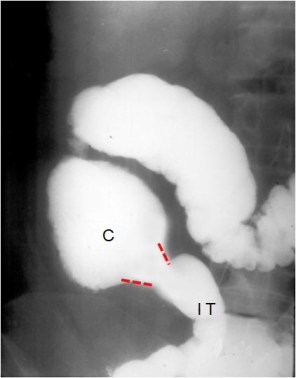

SIGNO DE FLEISHNER o SIGNO DEL PARAGUAS INVERTIDO

Signo de tuberculosis que afecta a la válvula ileocecal, en el estudio baritado. El signo consiste en la apertura amplia de la válvula asociada a un estrechamiento de luz del íleon terminal. El aspecto es el de un paraguas invertido, con la tela vuelta del revés. Este signo no es específico de tuberculosis ileocecal, ya que también puede estar presente en algunos pacientes con enfermedad de Crohn severa.

La imagen muestra un paciente con afectación tuberculosa de la válvula, que muestra una amplia apertura, pero no existe estrechamiento de la luz ileal.